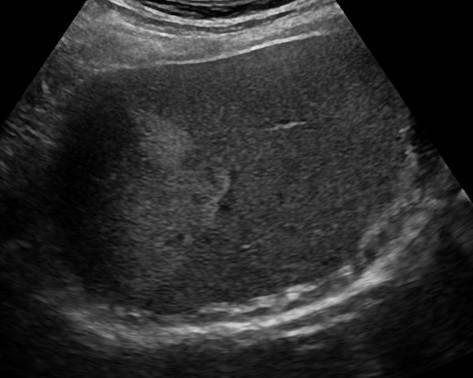

Gan nhiễm mỡ - Ảnh 3

Gan nhiễm mỡ

» Thông tin: Nam giới – 42 tuổi.

» Lâm sàng: Kiểm tra sức khỏe.